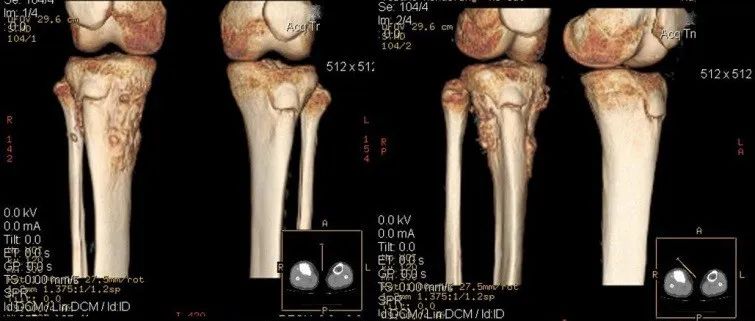

软骨肉瘤好发于骨盆, 也可发生在股骨、胫骨等长骨的干骺端和肩胛骨等处。而发生于肋骨者少见, 我科收治了 1 例肋软骨肉瘤, 现报告如下。病例资料患者,女,48 岁,系体检发现左第六后肋肿物入院。图 A、B:术前 CT、MR 检查胸椎 CT 检查提示:左第六后肋肿物,骨巨细胞瘤细胞瘤待排。MR 示:T6 椎体水平左侧脊柱旁占位灶,考虑骨巨细胞瘤细胞瘤可能大 (图 A、B)。术前血常规、凝血、肝肾功能、肿瘤标志物未见异常,行 CT 下定位并标记,因肿物靠近胸主动脉,邀请胸外科联合手术治疗,排除手术禁忌后,于 2018 年 3 月 19 日在全麻下行左第六后肋肿物扩大切除术。...